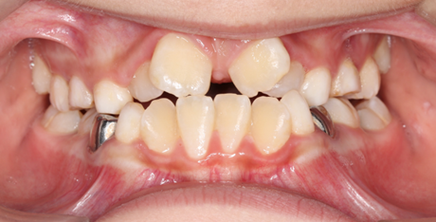

临床表现涉及牙齿、颌骨及面部软组织多个层面,牙齿层面,最典型的是上颌前牙唇倾、深覆盖(上前牙切端至下前牙唇面的水平距离超过3mm),常伴有深覆颌(上前牙切端覆盖下前牙冠长度1/3以上),磨牙呈完全远中或远中尖对尖关系;部分患者可能出现上牙弓狭窄、牙列拥挤,颌骨层面,上颌骨可能发育正常或前突,下颌骨发育不足,表现为下颌后缩、颏部后缩,侧面观面下1/3高度不足,下颌平面角可能增大或正常,软组织层面,患者常表现为鼻唇沟加深、上唇短缩、上唇相对于下唇前突,微笑时可能露龈,颏唇沟变浅,严重者可出现“鸟嘴”样面型,功能层面,由于咬合关系异常,咀嚼效率降低,长期可能引发颞下颌关节弹响、疼痛,甚至肌肉疲劳。

从分类上看,二类错颌畸形通常分为两个亚类:二类一分和二类二分,二类一分是指磨牙呈远中关系,且上下牙弓中线一致,临床常见上颌前牙唇倾或双牙弓前突,患者侧面观呈凸面型,上唇相对下唇前突;二类二类则指磨牙远中关系伴上下牙弓中线不一致,通常上颌中线偏斜,可能由单侧上颌前突、下颌偏斜或两侧下颌发育不对称导致,常伴有颜面不对称,两类亚类的治疗目标和侧重点有所不同,二类一分更侧重于改善覆盖和磨牙关系,二类二类则需兼顾中线对称和颌骨协调。